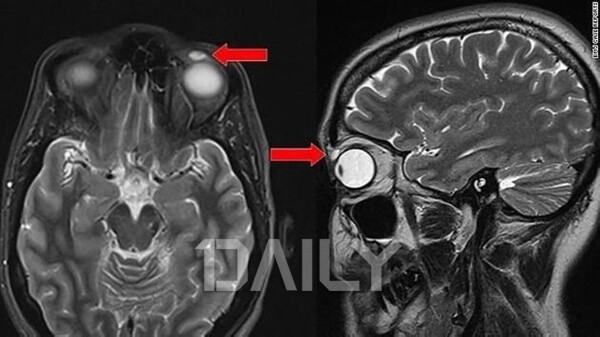

»çÁø: BMJ CASE REPORTS

¸î ³â Àü ¿µ±¹ ¿Ü½ÅµéÀº ½ºÄÚÆ²·£µå ´øµð¿¡ »ç´Â 42¼¼ ¿©¼ºÀÇ ´«¿¡¼ 28³âÀ̳ª ¹¬Àº ÄÜÅÃÆ®·»Á ¹ß°ßÇß´Ù°í º¸µµÇß´Ù. ±×´Â ¾î´À ³¯ ¿ÞÂÊ ´«²¨Ç® À§ÂÊ ºÎºÐ¿¡ ÄḸ ÇÑ µ¢¾î¸®°¡ ´À²¸Áö´Â °ÍÀ» ¹ß°ßÇߴµ¥, ¸¸Áö¸é ¾ÆÇÁ°í, µ¢¾î¸® ÁÖº¯À¸·Î ´«²¨Ç®µµ Á¶±Ý¾¿ óÁö±â ½ÃÀÛÇß´Ù°í ÀüÇß´Ù. ÀÌ¿¡ º´¿ø¿¡¼ ¹°È¤ÀÎ °Í °°´Ù´Â Áø´ÜÀ» ¹Þ°í ¼ö¼úÀ» ÁøÇàÇØº¸´Ï 'ÄÜÅÃÆ®·»Áî', Àϸí 'Çϵ巻Áî'¿´´Ù°í ÇÑ´Ù. ÀÌ ¿©¼ºÀÇ ¾î¸Ó´Ï´Â 'µþÀÌ 14»ìÀÏ ¶§ ¹èµå¹ÎÅÏÀ» Ä¡´Ù°¡ ÄÜÅÃÆ®·»Á ÀÒ¾î¹ö·È´Ù'¶ó°í ÀüÇß´Ù. ´ç½Ã ±×´Â ´«¿¡ À̹°°¨ÀÌ ¾ø¾î ÄÜÅÃÆ®·»Áî°¡ ¶¥¿¡ ¶³¾îÁø ÁÙ ¾Ë¾ÒÀ¸¸ç ±× ÀÌÈÄ¿¡µµ ÁÙ°ð ÀÌ»óÀ» ´À³¢Áö ¸øÇß´Ù°í ÇÑ´Ù.

¿µ±¹ ÀÇÇÐÀú³Î 'BMJ Case Reports'¿¡ º¸°íµÈ ¹Ù¿¡ µû¸£¸é "ȯÀÚ´Â »ç°í ÀÌÈÄ »ê¼ÒÅõ°ú¼º ·»Á ´Ù½Ã´Â »ç¿ëÇÏÁö ¾Ê¾Ò´Ù. »ç°í ´ç½Ã ·»Áî°¡ ±×³àÀÇ ´«²¨Ç®·Î ¿Å°å°¬À¸¸ç ±× »óÅ·ΠÁö³ 28³â°£ ±× ¾È¿¡ ¼û¾îÀÖ¾ú´ø °ÍÀ¸·Î ÃßÁ¤µÈ´Ù."¶ó°í ÀüÇß´Ù. ÀÌÈÄ ·»Áî¿Í ·»Áî·Î ÀÎÇÑ ³¶Á¾À» Á¦°ÅÇÏÀÚ ¿©¼ºÀÇ ´«²¨Ç®Àº Á¤»óÀ¸·Î µ¹¾Æ°¬´Ù°í ¾Ë·ÁÁ³°í, ÀÌ »ç·Ê´Â ÇöÀç±îÁö 'ÇÏµå ·»Áî°¡ °¡Àå ¿À·§µ¿¾È ´« ¾È¿¡ ¸Ó¹® »ç·Ê'·Î ±â·ÏµÆ´Ù. ¹®Á¦´Â °£È¤ ÀϺΠ´º½º¿¡¼ '´« µÚ·Î ·»Áî°¡ µ¹¾Æ°¬´Ù'°í Ç¥ÇöÇÏ¸é¼ »ç½ÇÀÌ ¿Ö°îµÈ °ÍÀ¸·Î º¸ÀδÙ. ÀÌ ¿©¼ºÀÇ °æ¿ì ·»Áî°¡ ´« µÚ·Î µ¹¾Æ°£ °ÍÀÌ ¾Æ´Ñ ´«²¨Ç® À§ÂÊ¿¡¼ ¹ß°ßµÈ °ÍÀÌ´Ù.